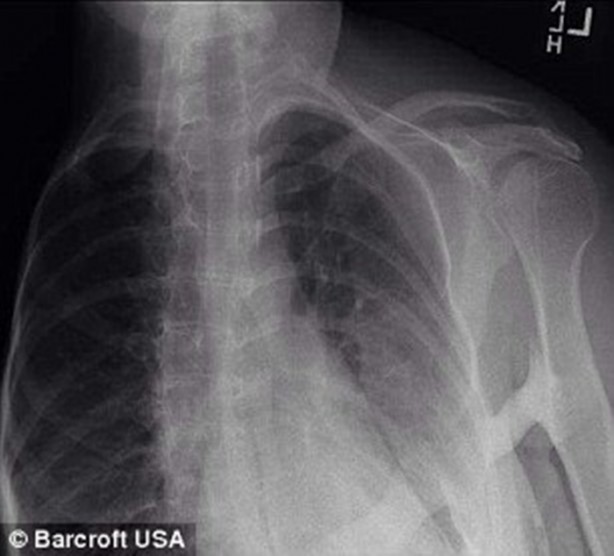

F.O.P oldukça nadir görülen ve bağ dokunun kemikleşmesiyle karakterize olmuş bir hastalık.

Beş ay sonrasında ise doktorlar Ashley'e yanlış teşhis koyduklarını ve dünyada iki milyonda bir görülen Fibrodysplasia Ossificans Progressiva hastalığına yakalandığını söyledi.

Dünya genelinde bu hastalığa sahip yaklaşık 800 kişinin var olduğu tahmin edilmektedir. F.O.P hastalığının neden olduğu henüz netleştirilememiş bir konudur, ancak genetik olabileceği düşünülmektedir. Hastalık özellikle çocukluk ve ergenlik döneminde atağa geçebilir.

Hastalığın gelişiminde, normalde bağ doku olarak kalması gereken bölgelerin kemikleştiği görülür. Bu durum sonrasında F.O.P hastalığına sahip kişinin hareket kabiliyeti büyük oranda engellenir ve iç organların çalışmasında da ciddi zorluklar yaşanır.

Hastalığın gelişimini haber veren ciddi bir belirti yoktur. Tek belirti özellikle ayak başparmaklarının eklemlerin tutulması nedeniyle kıvrılmaması durumudur.

Hastalığın tedavisinde oluşan kemiklerin alımı ve kemik gelişimini yavaşlatan ilaçların uygulanması gibi yöntemler uygulansa da tam bir iyileşme tedavisi henüz bulunmamaktadır.